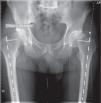

Noveno pasoSe añade un texto a la planificación donde se anota el tipo de vástago, su tamaño, el offset a utilizar (estándar o lateralizado), el tipo y tamaño del cotilo, el tamaño del cuello, la lateralidad de la cirugía y, opcionalmente, el nombre del paciente (fig. 5). Con este paso la planificación se da por finalizada.